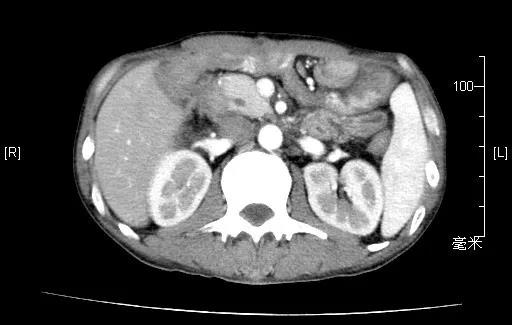

2020.03.10术后基线腹部CT

2020.05.26腹部CT(化疗3周期后)